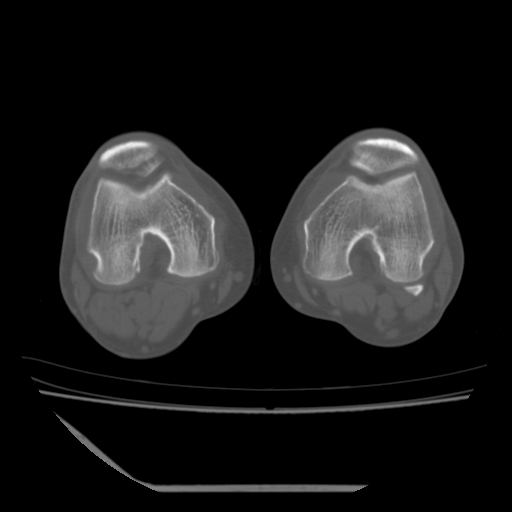

标题: CT13225:老年男性,左膝关节疼痛数月;请各位老师讨论。 [打印本页]

标题: CT13225:老年男性,左膝关节疼痛数月;请各位老师讨论。

骨质增生,骨性关节面硬化,关节积液,考虑退行性骨关节病

关节腔内少量积液,关节面退变。

双膝退变

骨质增生,骨性关节面硬化,关节间隙失常,关节积液,考虑退行性骨关节病.

这是由于两侧的肌肉不对称所致,加上扫描的平面也有些差异。请看示意图:

这个病例诊断:退行性骨关节炎